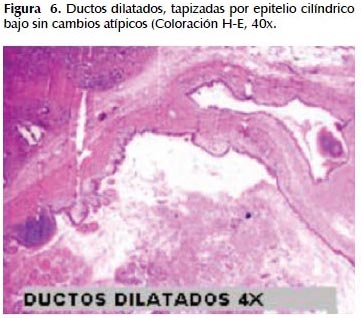

La alteración fundamental en este caso es la presencia de marcada dilatación de los conductos pancreáticos (Figuras 6, 7, 8, 9, 10 y 11) con variable hiperplasia de los conductos menores periféricos.

Los quistes están limitados por células ductales altas, algunas mucinosas, en su mayor extensión dispuestas en una fila. De manera focal se ve proyecciones papilares del epitelio y también focos de erosión con reacción inflamatoria, exudado linfocitario y formación de tejido de granulación.

El resto del parénquima pancreático muestra múltiples focos de autolisis y variable hiperplasia de los ductos.